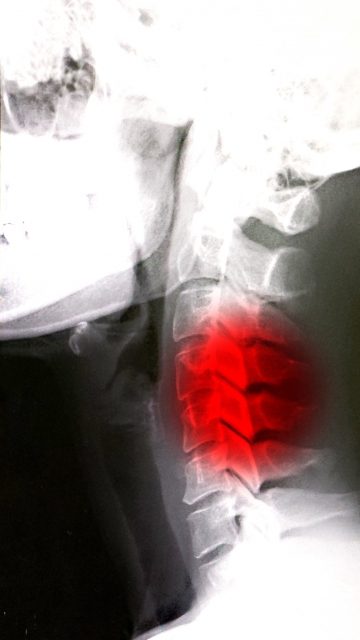

首こり・肩こりが頭痛を起こすメカニズム

首や肩の筋肉が硬くなると、筋肉の中を通る血管や神経が圧迫され、頭部への血流が低下します。

その結果、脳への酸素供給が減少し、**「締めつけられるような頭痛(緊張型頭痛)」**が起こります。

さらに、長時間の姿勢不良やストレスで自律神経が乱れると、首から後頭部にかけての神経が過敏になり、慢性的な頭痛を感じやすくなります。